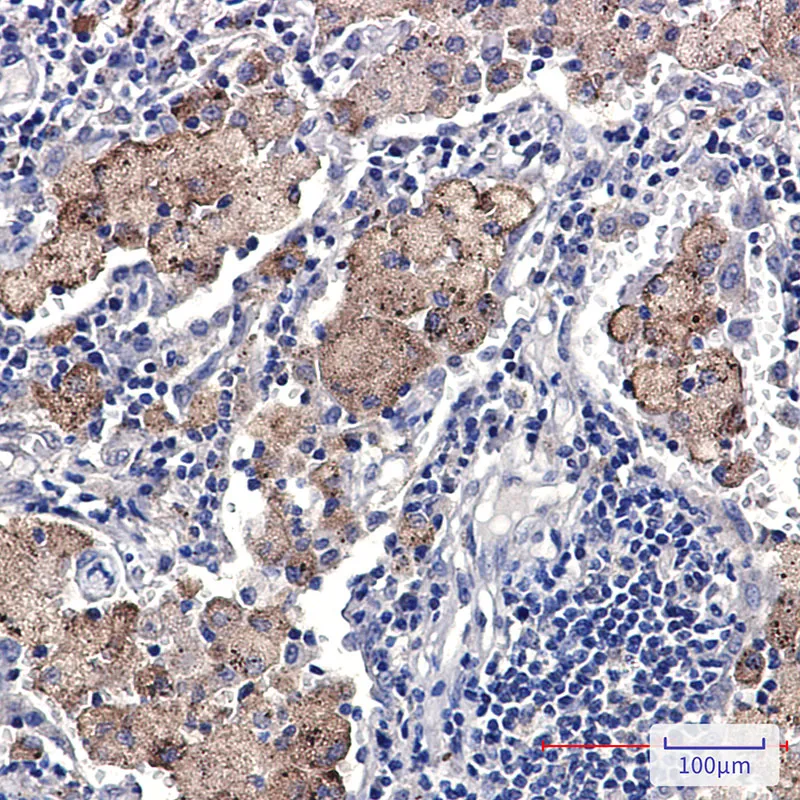

SMN Rabbit Monoclonal Antibody

Cat: AMRe02028

Size1:50μL Price1:$158

Size2:100μL Price1:$288

Size3:500μL Price1:$288

Application:WB,IHC-P,IP

Reactivity:Human

Conjugate:Unconjugated

Gene Name:SMN1

Size2:100μL Price1:$288

Size3:500μL Price1:$288

Application:WB,IHC-P,IP

Reactivity:Human

Conjugate:Unconjugated

Gene Name:SMN1